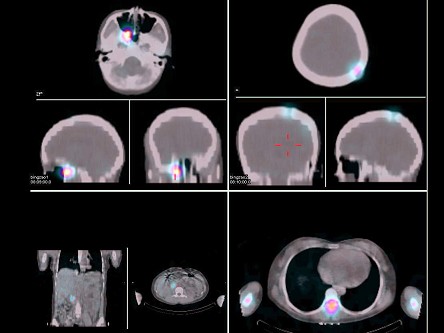

女,22岁,阵发性高血压2年,间歇性头痛、胸背痛半年,CT示右肾门区占位病变,行[131I-MIBG全身显像+局部X线定位及99Tcm-MDP骨显像如图,可能的诊断是 ( )

多选题 12-09 做题人次:1160